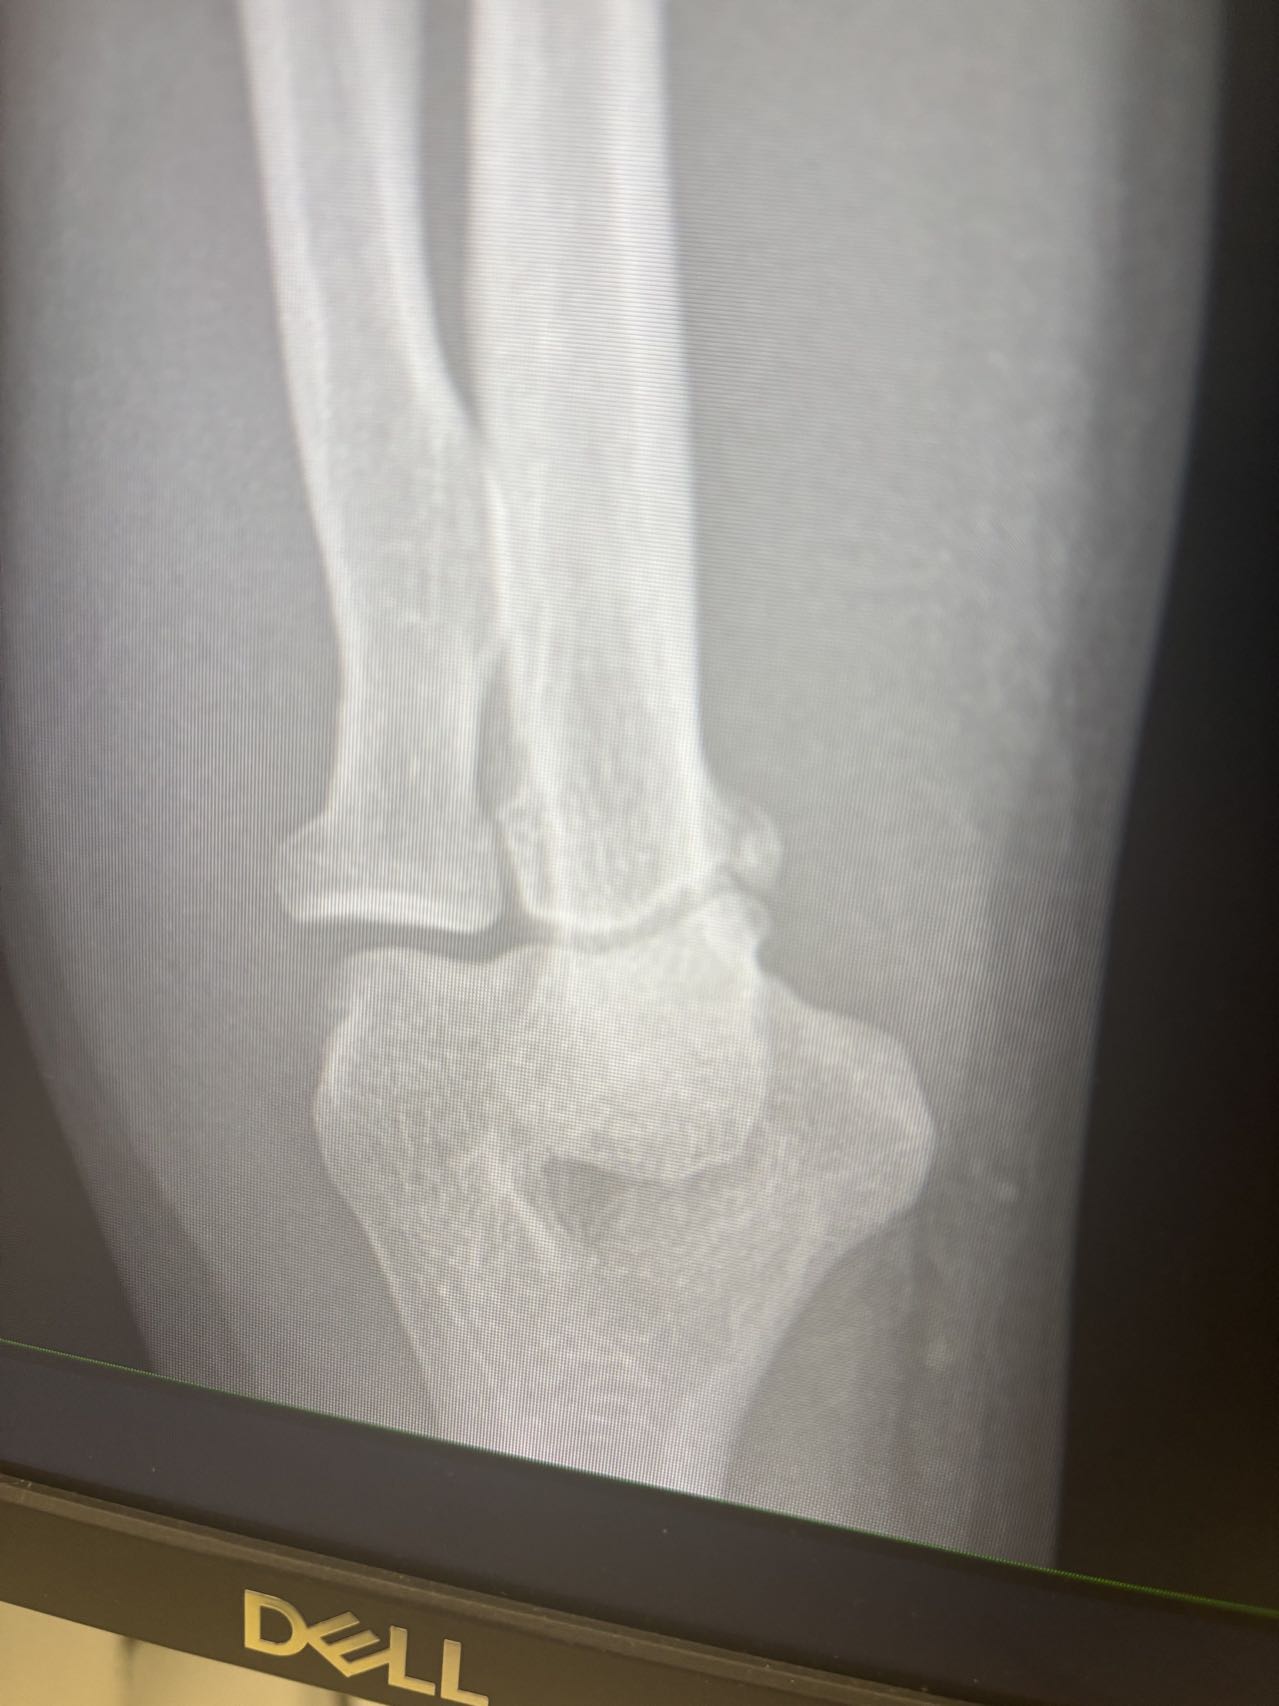

回来拍了片子,elbow还是fracture了